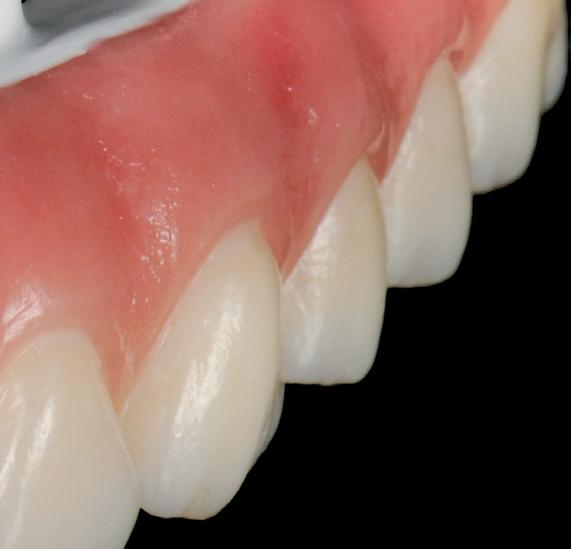

In the ALPHA TO OMEGA OF VENEERS, Dr Lazaris shares his unique, aesthetically-driven protocols and digital workflows as a unified system developed specifically to enhance clinical efficiency and predictability and eliminate any margin for error. Structured in a modular sequence, each topic is delivered as a step in a methodical, reverse-engineering process that maps out a logical pathway to achieving superior treatment outcomes with precision and confidence. Honed through comprehensive critical analysis and evolution, these protocols are universally applicable to every dentist, every patient and every case...

Angelo has developed his own complete digital protocols from inception and design through to delivery and integrated these with biomimetic adhesive dentistry and contemporary restorative materials to create a complete clinical workflow that is equally applicable to single restorations, through to complex full mouth rehabilitations, culminating in outstanding clinical outcomes in a real-world commercial environment. His innovative approach to clinical dentistry is to start at the desired